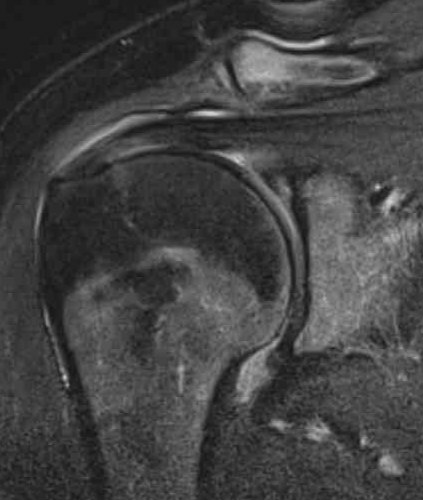

MRI

Thickened capsule and synovitis of axillary capsular recess